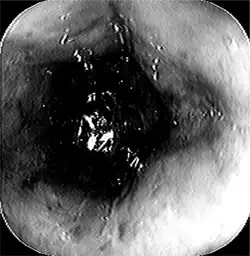

Esophageal disease

| Head and neck. Esophagus at bottom. | |